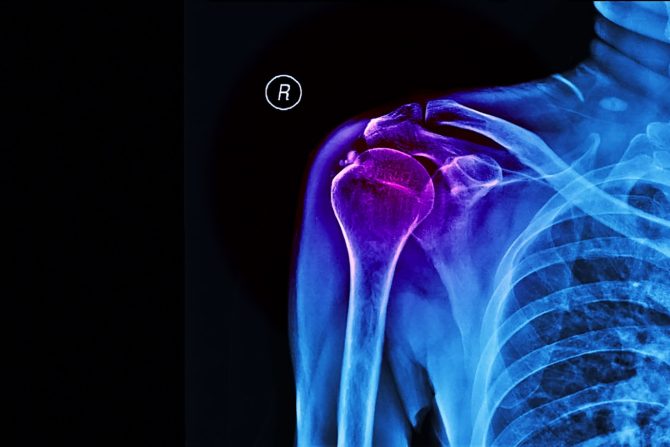

Kalcifikacija ramena je stanje koje se javlja kada se kalcijum, a nekad i drugi minerali, talože u mekim tkivima, tetivama oko ramena i predstavlja vodeći uzrok bolova u ramenu. Može da se pojavi u tetivama ili ligamentima rotatorne manžetne i izazove bol, otečenost i smanjenu pokretljivost. Kalcificirajuća tendinopatija, odnosno pojava kalcifikata u tetivama mišića različitih delova tela, relativno je česta, a njen uzrok često ostaje nepoznat.

Kada se govori o regiji gde nastaje, razlikuju se dva glavna tipa kalcifikacije ramena  - distalna i proksimalna kalcifikacija. Distalna kalcifikacija nastaje kada se taloženje kalcijuma javi bliže glavi humerusa (nadlaktične kosti), dok se proksimalna kalcifikacija javlja bliže gornjem delu lopatice. Lekari ističu da u kojoj god regiji da se javi stvaranje kalcifikata u ramenu otežava pokretljivost i stvara osećaj intenzivnog bola.